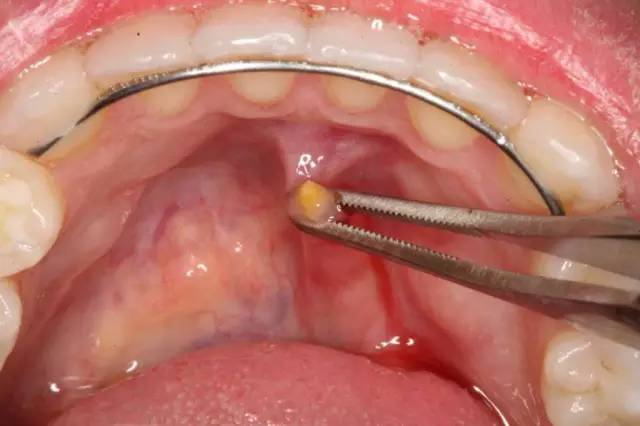

口腔科医生首先可能尝试使用细长锋利的工具来探寻唾液导管,移除结石。

如果借助探针没有用,就需要使用涎腺内窥镜进行手术治疗。首先对嘴部进行局部麻醉,然后将带有微型内窥镜的细管插入涎腺导管。如果发现了唾液腺结石,就能使用细管一端的微型工具将其移除。